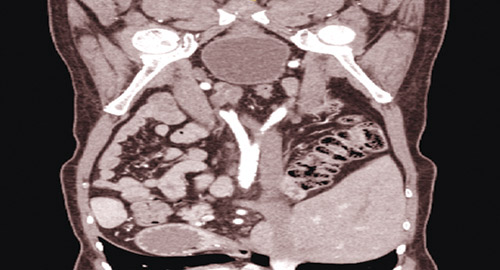

وأضاف د. عزام أن الفريق الطبي قسم الخطة العلاجية إلى جزءين وركز في الأول على علاج مشاكل القلب والجلطات وتكثيف عمليات الغسيل، لمدة «6» أشهر، وتحسنت خلالها الحالة الصحية له، فقام الفريق الطبي الذي ضم طيفاً واسعاً من التخصصات، بإعادة تقييم وفحص التحاليل والصور الطبية، ودراسة ملف الحالة، لمعرفة ملاءمة المريض الطبية والجراحية للزراعة، وخلص إلى أنه لم يعد هناك مانع صريح لعملية زراعة الكلى، فتم وضع خطة علاجية متكاملة، واطلاع المريض وذويه على تفاصيلها كافة، ومن ثم تم إخضاع المريض والمتبرع لعمليتين استمرتا نحو «6» ساعات، ومضتا -ولله الحمد- بسلاسة تامة، وكللتا في النهاية بالنجاح الكامل، حيث استجابت الكلية المزروعة بشكل فوري و»تبول» المريض وهو لا يزال في غرفة العمليات، وفوق ذلك فإن تحاليل ما بعد العملية بينت تناقصاً لافتاً وتدريجياً في سموم الكلى، ولم يحتاج إلى الغسيل مطلقاً بعد الزراعة وقد خرجت المتبرعة بعد «3» أيام من العملية التي تمت عن طريق المنظار وهي بحالة جيدة ودون مضاعفات، وتابع د. عزام قائلاً إن العملية كانت من أكثر عمليات زراعة الكلى تعقيداً، وهو ما دفع أكثر من مستشفى ومركز متخصص بارز إلى رفض إجرائها، فبالإضافة إلى الإشكالات التي أشرنا لها، تبين أن المريض أيضاً يعاني من جلطات في الناحية اليمنى التي عادة يتم فيها زراعة الكلية، كما ظهرت تعقيدات تقنية خاصة بالمتبرع حالت دون تمكن الفريق الطبي من أخذ الكلية اليسرى، فتم استئصال اليمنى وزراعتها في الجهة اليسرى لمنطقة الحوض.